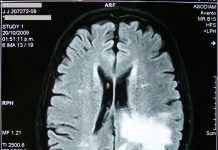

CRUK launches £18m Brain Tumour Awards

The Cancer Research UK (CRUK) Brain Tumour Awards have been launched today, with the aim of funding and tackling six major themes in brain...

Flu-like virus being used to fight incurable brain cancer

UK scientists are optimistic that using a common flu-like virus is the next best treatment to help tackle incurable brain cancer.

According to recent studies,...